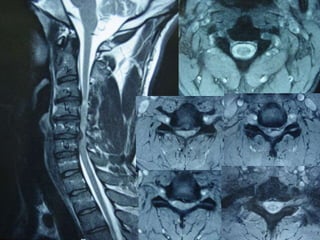

48 year old man with three week H/O severe neck pain with no improvement with

2 weeks of prednisone/narcotics/muscle relaxers

75 year old man severe neck pain

21 male severe! neck pain for three months with multiple ER

visits for narcotics/physical therapy visits/feels clumsy/ three

day history of difficulty walking following fall